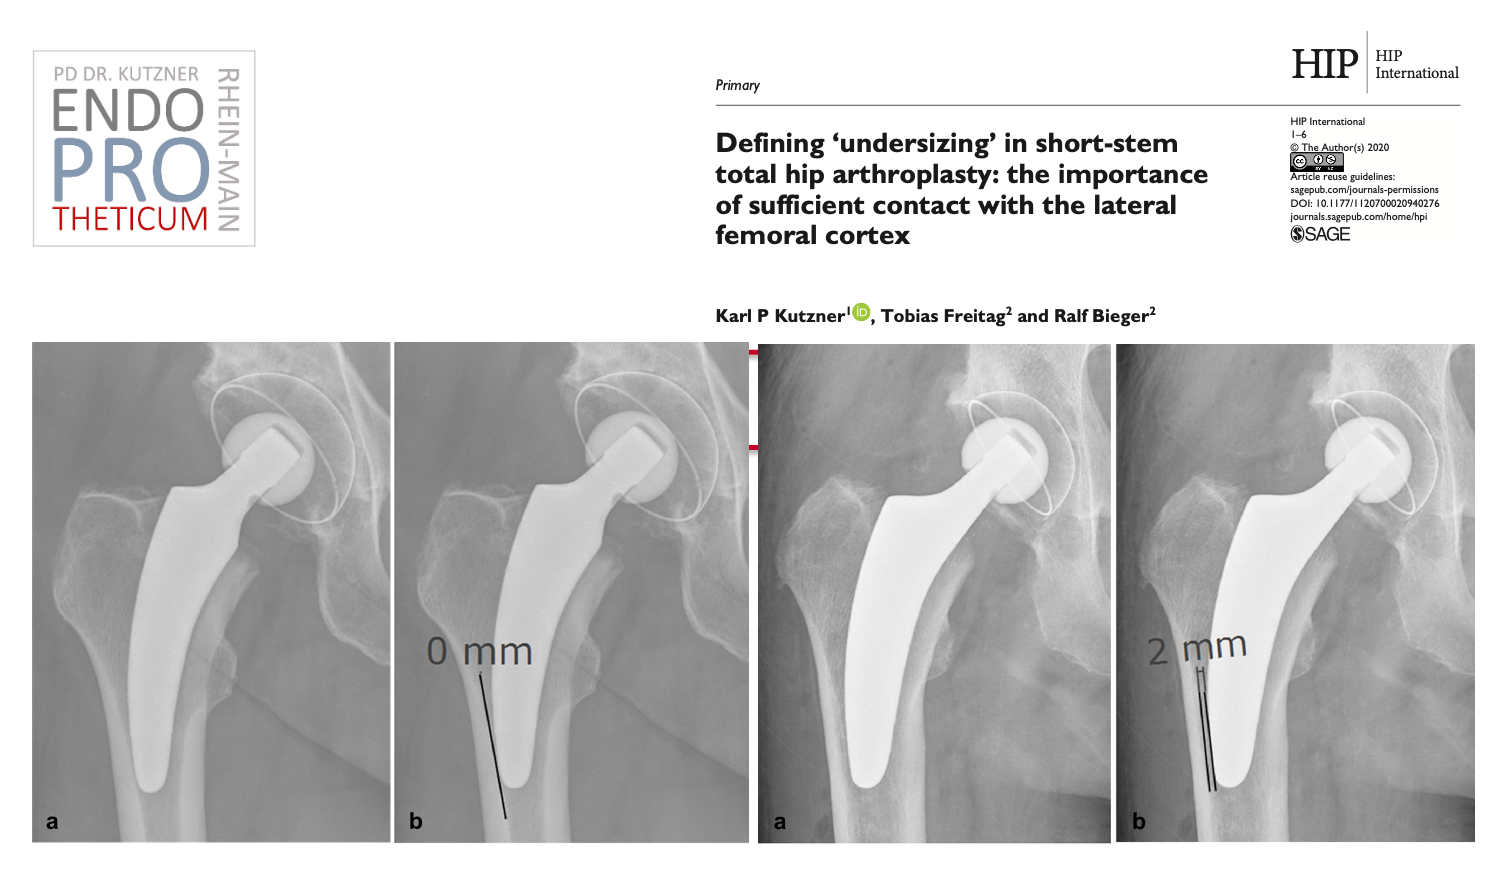

يهدف مفهوم السيقان القصيرة الحديثة الموجهة بالكلس في جراحة مفاصل الورك إلى إعادة البناء الدقيق لهندسة الورك التشريحية الفردية. يتم استخدام تقنية زرع لطيفة على العظام والأنسجة الرخوة بالتزامن مع التحميل الفسيولوجي في جزء عظم الفخذ بالقرب من المفصل من أجل الحفاظ على العظام على المدى الطويل.